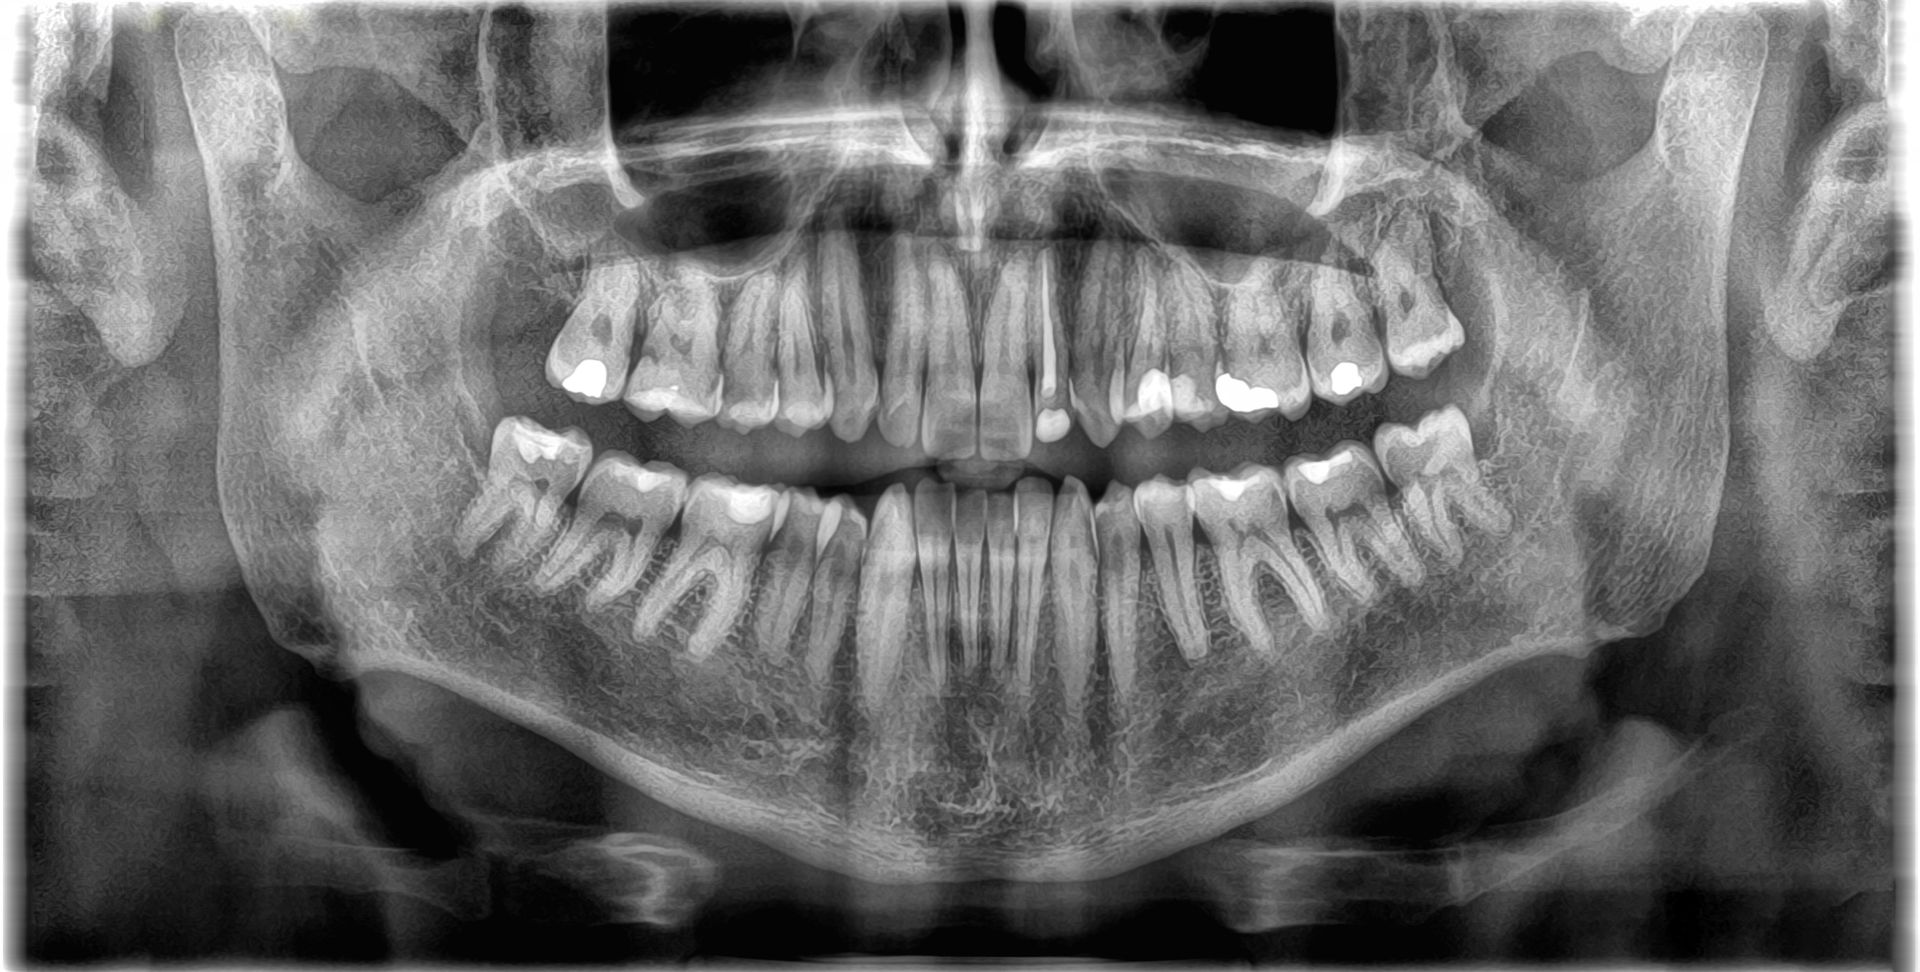

We may also recommend a panoramic x-ray to provide a wraparound view of the jaw joints, sinus areas, the roots of the teeth, and the location of the inferior alveolar canal (a large canal in the lower jaw carrying a major nerve and blood vessel to supply the gums and teeth in the lower jaw) and wisdom teeth. These anatomical structures are not visible on regular small checkup x-rays.